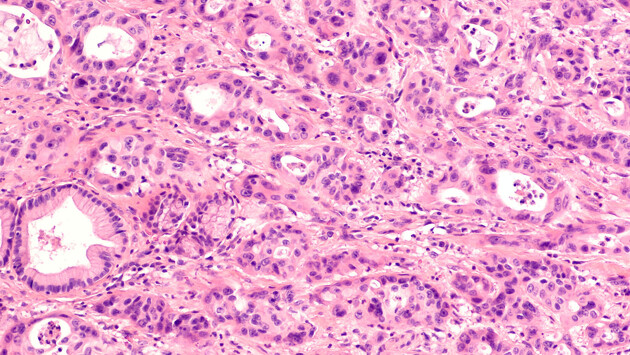

Шведские ученые из Лундского университета нашли способ лишить раковые опухоли защитного барьера, не дающего иммунной системе организма уничтожать онкологические новообразования. Исследование опубликовано в научном журнале Science.

Новый подход включает перепрограммирование раковых клеток в иммунные клетки cDC1, которые разрушают щит вокруг опухоли и позволяют Т-клеткам иммунитета устранить пораженные ткани.